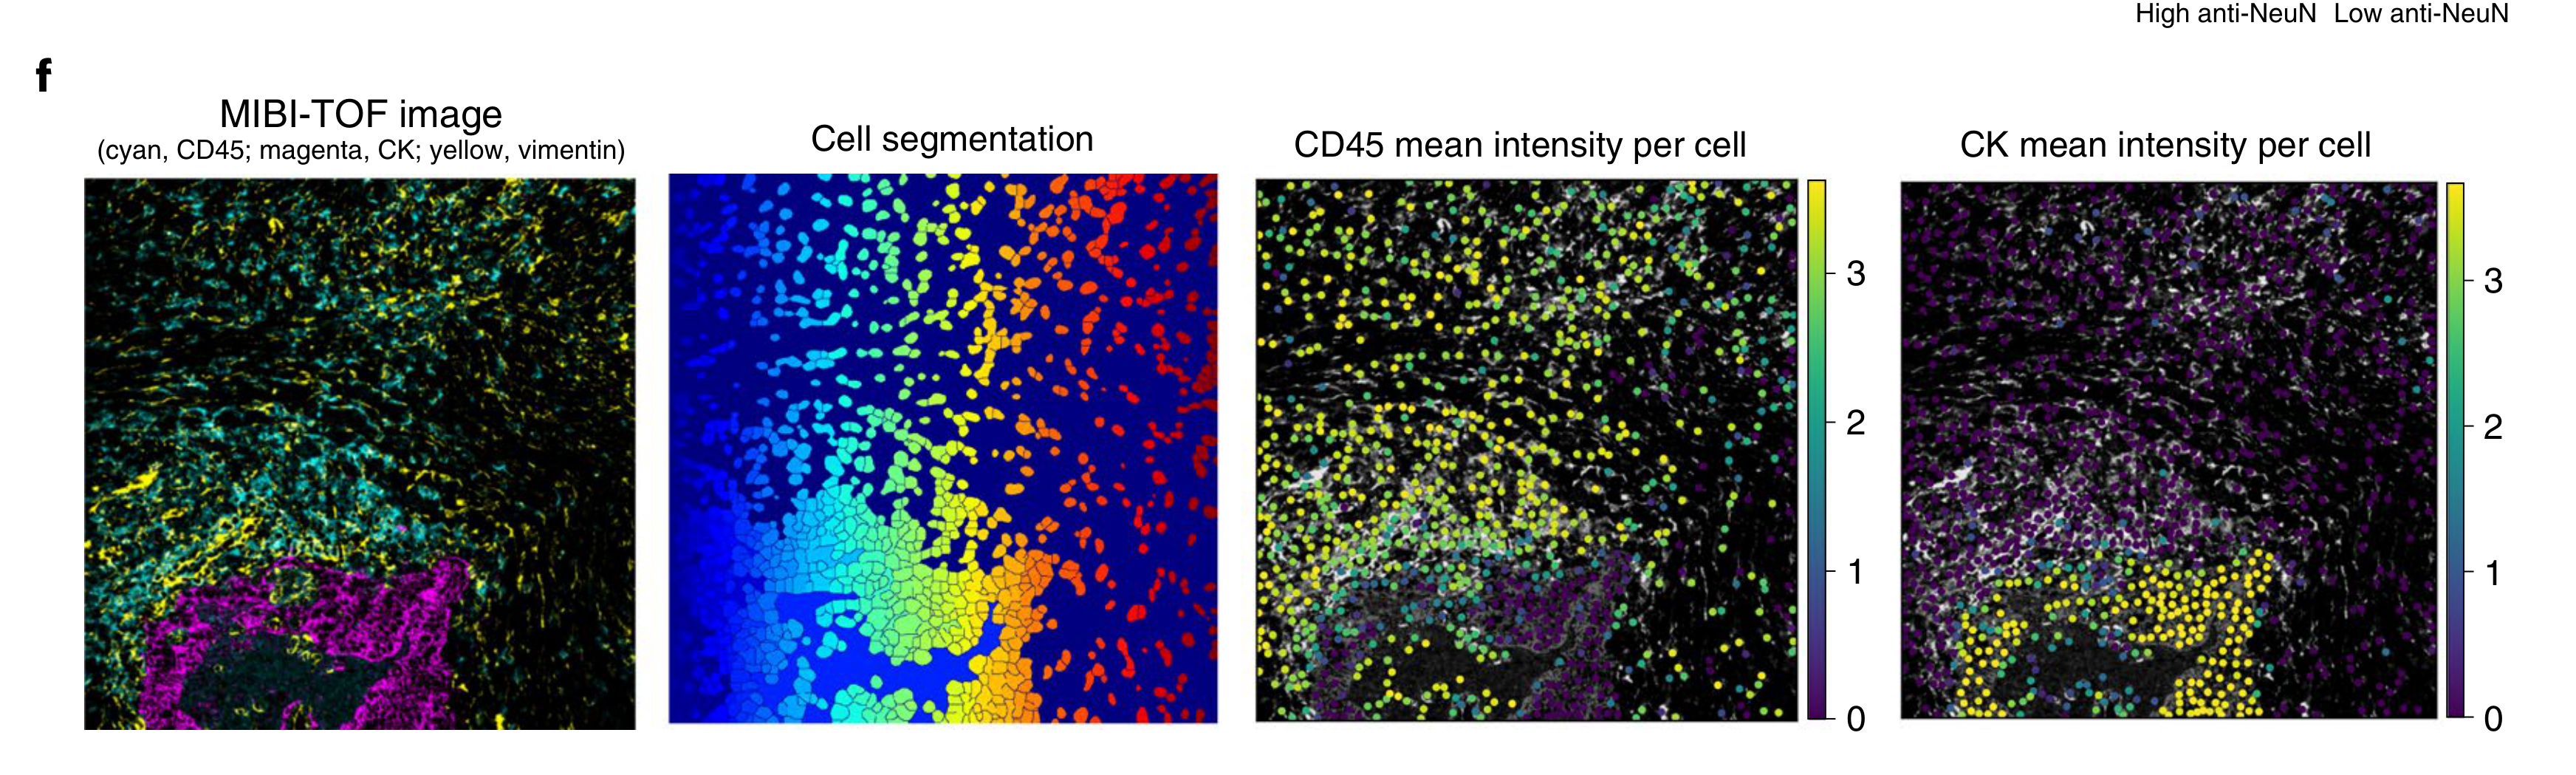

Li X. et al. - 2025

SPEX: A modular end-to-end platform for high-plex tissue spatial omics analysis

Condition Dimension

N/A

Data Components

Gene Expression Matrix

Data

Metadata

None

Modality

Proteomics

Resolution of observation

Cellular

Visualized Elements

FeatureObservation

Biological

Molecular

Abstraction

CompleteNone

Chart Type

Dimensionality reductionScatterplotSpatial Gene Expression Map

Communicative/Contextualization

Annotation

Comparative Design

JuxtapositionJuxtaposition : Small multiples

Layout

Spatial : LatentSpatial : Physical

Scalability Strategy

Sampling/Filtering

Where are specific proteins expressed in both expression space and physical tissue space?